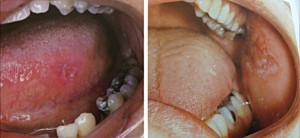

Клиническая картина. В полости рта и на коже лица наиболее часто встречается в хронической дискоидной форме. На лице — очаги поражения в виде резко очерченных с периферическим ростом розово-красных, шелушащихся пятен с тенденцией к слиянию. В очагах поражения различают три зоны: в центре — рубцовая атрофия, далее-гиперкератоз и по периферии-гиперемия. Удаление чешуек сопровождается резкой болезненностью. Слившиеся очаги поражения на щеках и переносице по форме напоминают фигуру бабочки. На слизистой оболочке очаги поражения утрачивают характерные признаки и проявляются гиперкератозом и гиперемией на фоне значительно инфильтрированной опалесцирующей слизистой оболочки чаще дистального отдела щек, ретромолярной области, а также на красной кайме нижней губы. При эрозивно-язвенной форме заболевания язвы очень болезненные, глубокие, щелевидной формы. На красной кайме язвы покрываются корочками. Для заболевания характерны рецидивы.